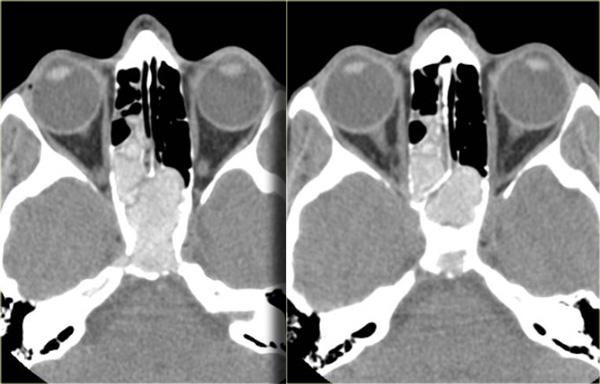

Bên trái là một trường hợp ban đầu được chẩn đoán nhầm là khối u.

Có vật chất tăng tỷ trọng ở xoang sàng sau bên phải, các ngách bướm-sàng hai bên, xoang bướm và có sự xâm lấn vào xương nền sọ (clivus).

Tình trạng tăng tỷ trọng là dấu hiệu tiên lượng tốt, gợi ý một quá trình lành tính.

Đây là ví dụ điển hình của viêm xoang nấm dị ứng.

Thông thường tổn thương này có vị trí ở phía trước hơn.

Bên trái là một ví dụ khác, điển hình hơn, của viêm xoang nấm dị ứng.

Có hình ảnh mờ đục hai bên hốc mũi, thường là dấu hiệu của quá trình viêm hoặc polyp.

Lưu ý hình ảnh phân lớp đồng tâm xen kẽ giữa tăng tỷ trọng và giảm tỷ trọng trong các xoang hàm.

Tình trạng tăng tỷ trọng là do dịch tiết đặc quánh và các thành phần nấm.

Tình trạng giảm tỷ trọng phản ánh các nang, bệnh lý niêm mạc và mô hạt.

Ở vùng xoang sàng, một phần tình trạng tăng tỷ trọng phản ánh viêm màng xương và tân tạo xương dọc theo các vách ngăn.